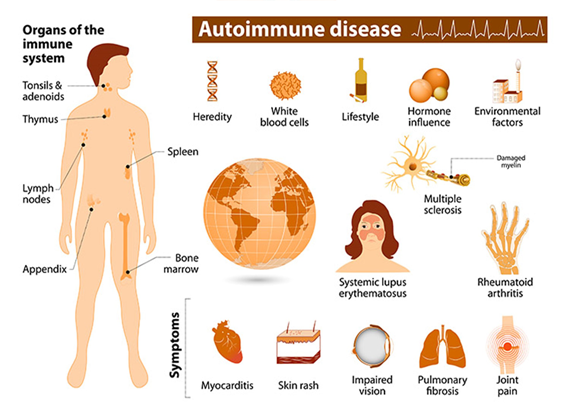

– Autoimmune disease